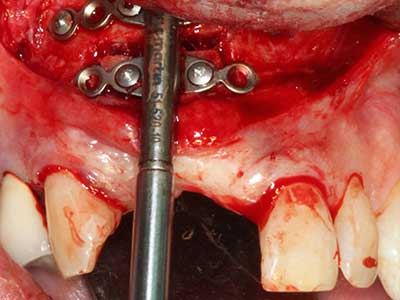

Si es preciso realizar intervenciones quirúrgicas en las que el hueso está en contacto directo con estructuras sensibles, como son los vasos sanguíneos o los nervios, los instrumentos rotativos presentan un enorme potencial de provocar lesiones iatrogénicas. Así, precisamente en la representación de nervios después de una lesión iatrogénica, o en el transcurso de la lateralización de un nervio para resecciones, reconstrucciones o incorporación de implantes, los equipos piezoeléctricos pueden resultar muy útiles para preparar la tapa ósea y retirar las partes de tejido duro cercanas al nervio (fig. 17-20). Por lo general, un ligero contacto del cordón nervioso con el inserto piezoeléctrico no tiene consecuencia alguna; ahora bien, un procedimiento poco cuidadoso con movimientos tipo sierra o piezas de trabajo sobre la base ósea aún existente puede provocar lesiones nerviosas temporales o incluso permanentes. Con todo, el riesgo de sufrir una lesión de este tipo se considera significativamente inferior que en los casos en los que se utilizan sierras y fresas (Pereira, Gealh et al. 2014).